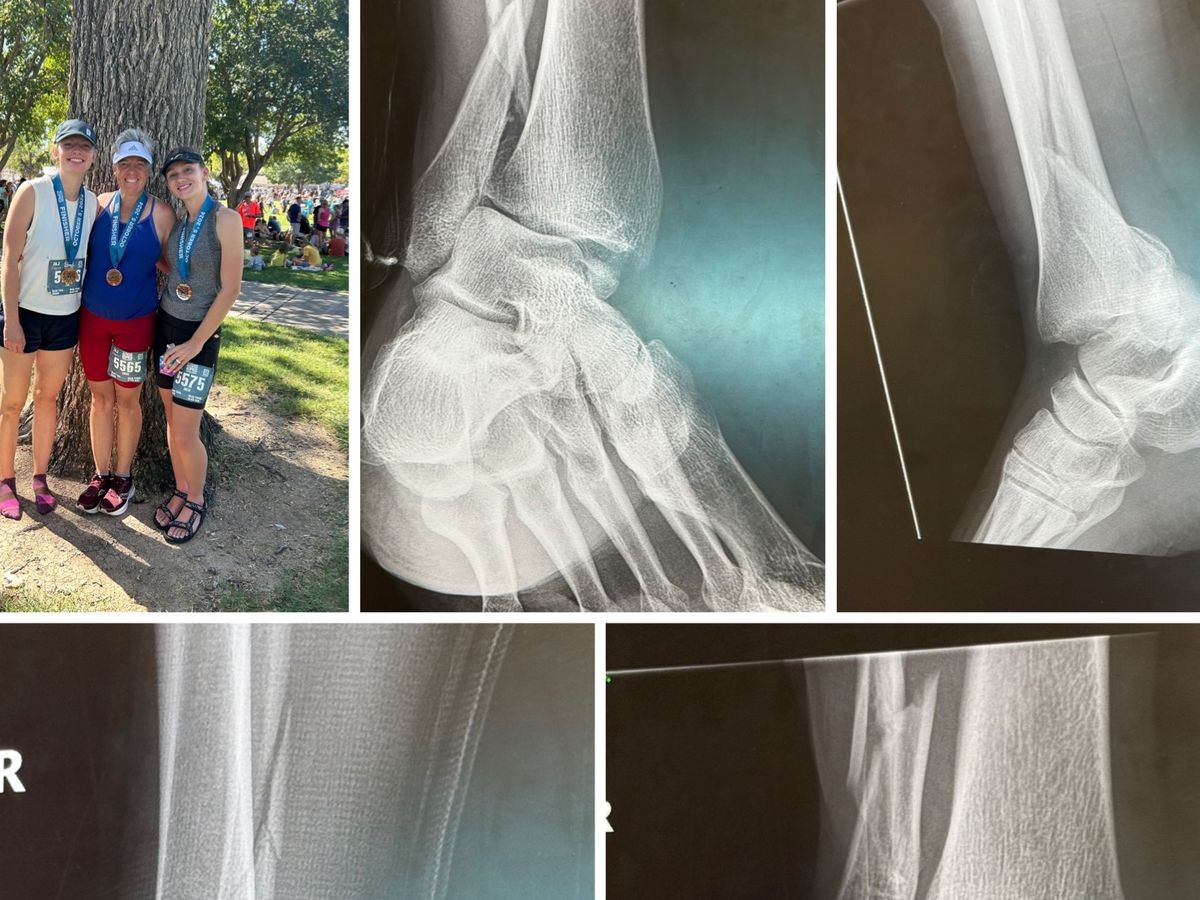

Unfortunately, last week, she suffered a devastating injury from slipping on the ice. What she initially thought was just a broken ankle turned out to be much worse—she broke all three bones that hold the ankle together, along with her tibia and fibula. Because of the severity of these breaks, she now needs surgery.

Without it, she faces a lifelong limp, arthritis in her ankle, and the heartbreaking possibility of never being able to trail run or hike again. Her surgery is scheduled for Wednesday, but the cost is more than she can manage on her own.